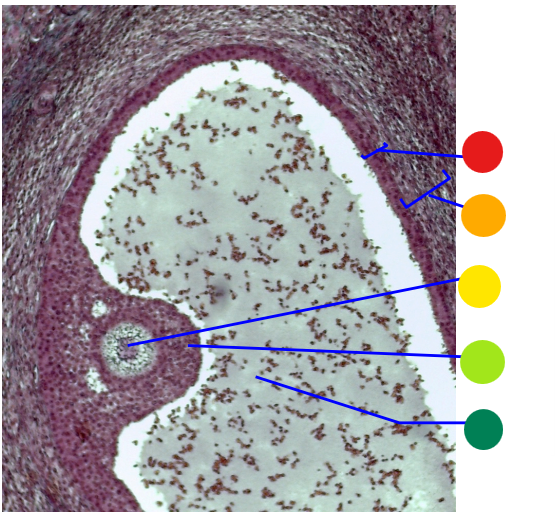

red

tunica albuginea

orange

primordial follicles

yellow

follicular cells

light green

primary oocyte

dark green

granulosa cells

light blue

primary follicles

what is this?

ovary